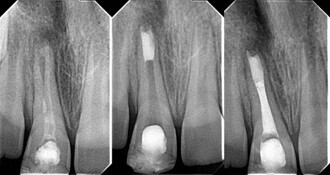

Revascularisation of the necrotic open apex

Two years ago, I was struggling to learn how to perform a good apical MTA plug. I used all the existing MTA carriers and absorbable barriers that I could ...